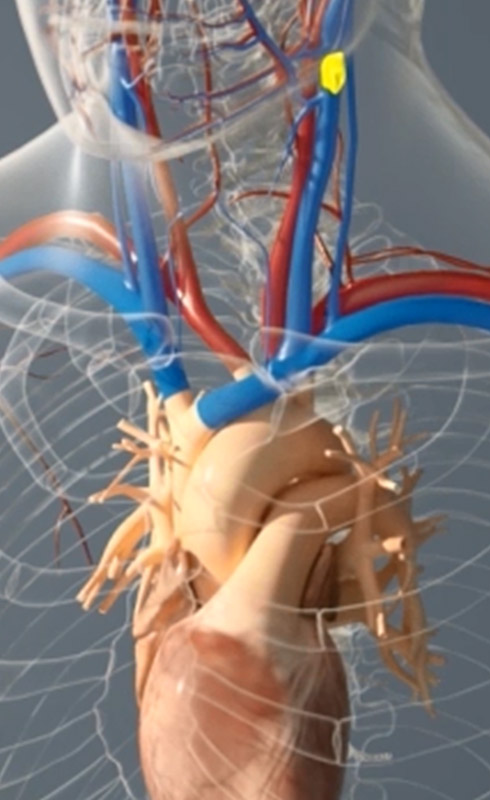

非弁膜症性心房細動の患者さんでは、脳卒中の原因となる血栓の90%以上が左心房に起始する左心耳(LAA:Left Atrial Appendage)で形成されたものです。

WATCHMANはこのLAAを閉鎖して血栓の形成を防ぎます。手技は経静脈的心房中隔穿刺法であり、カテーテル室において全身麻酔下で実施します。

心房細動によって心拍が不規則になり、心臓内の血流がよどみます。そうすると、血液が滞留して血栓が形成されることがあり、その血栓が心臓から出ていき、脳の血管を閉鎖すると脳卒中になります。

心房細動とはどのようなもの?

心房細動は、心臓の上部にある2つの部屋(心房)が小刻みで不規則な拍動(細動)をする不整脈です。この疾患によって、心臓の左心耳(LAA:Left Atrial Appendage)に血液が滞留して血栓が形成されることがあります。血栓が動脈を通って脳に達すると脳卒中に至る場合があります。

心房細動による脳卒中リスクはどの程度

心房細動は、心房のポンプ効率を最大30%も低下させます。ポンプ機能が不良であると、心臓で血栓が形成されるリスクが高まります。血栓が剥がれて血流に乗り、脳や肺などに移動することがあります。心房細動で最も多く、最も恐れられている合併症が脳卒中です。